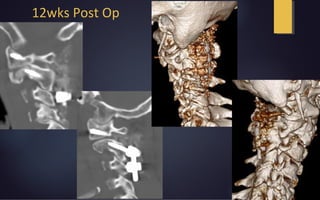

12wks Post Op

Traction & Reductionin Mayfield C1-3 Fusion Immediate Post-Op 4wk Post-Op